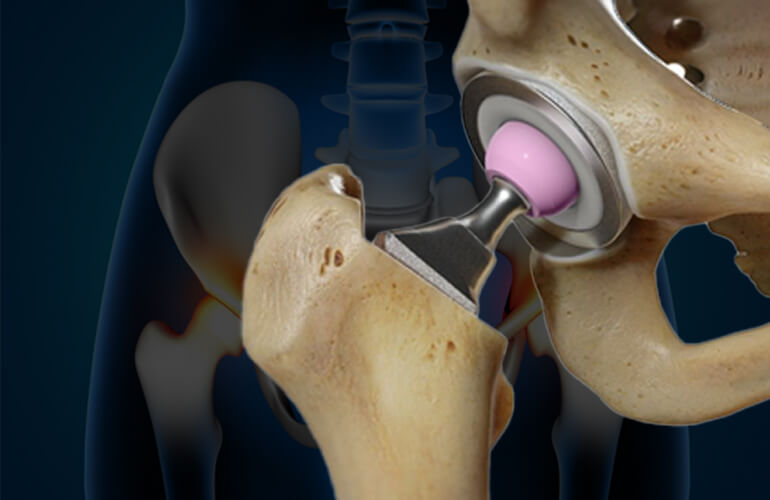

At Gifford Orthopaedics, we specialize in advanced treatments for hip and knee conditions, helping patients regain mobility and live without pain. Our services range from minimally invasive procedures to total joint replacements, all tailored to meet your unique needs.

Minimally invasive hip surgery reduces pain and speeds up recovery.

Simultaneous replacement of both hips, considered based on individual suitability.

Reoperation on previous hip replacements that have worn out, failed, or become loose.